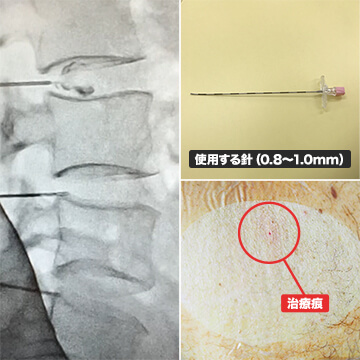

治療内容

損傷した椎間板に特殊な薬剤を入れ、椎間板機能の改善を目的とした治療方法です。特に変形したり、狭くなっている椎間板に対して治療を行っています。

-

- 効果

- 3~12ヵ月で症状の改善が期待できます。

-

- 副作用

- 治療後2週間程度は一時的に症状が悪化する可能性があります。また椎間板の容量が増えたことにより周りの筋肉や靭帯が広がることによって筋肉痛や腰の違和感が出現することがあります。